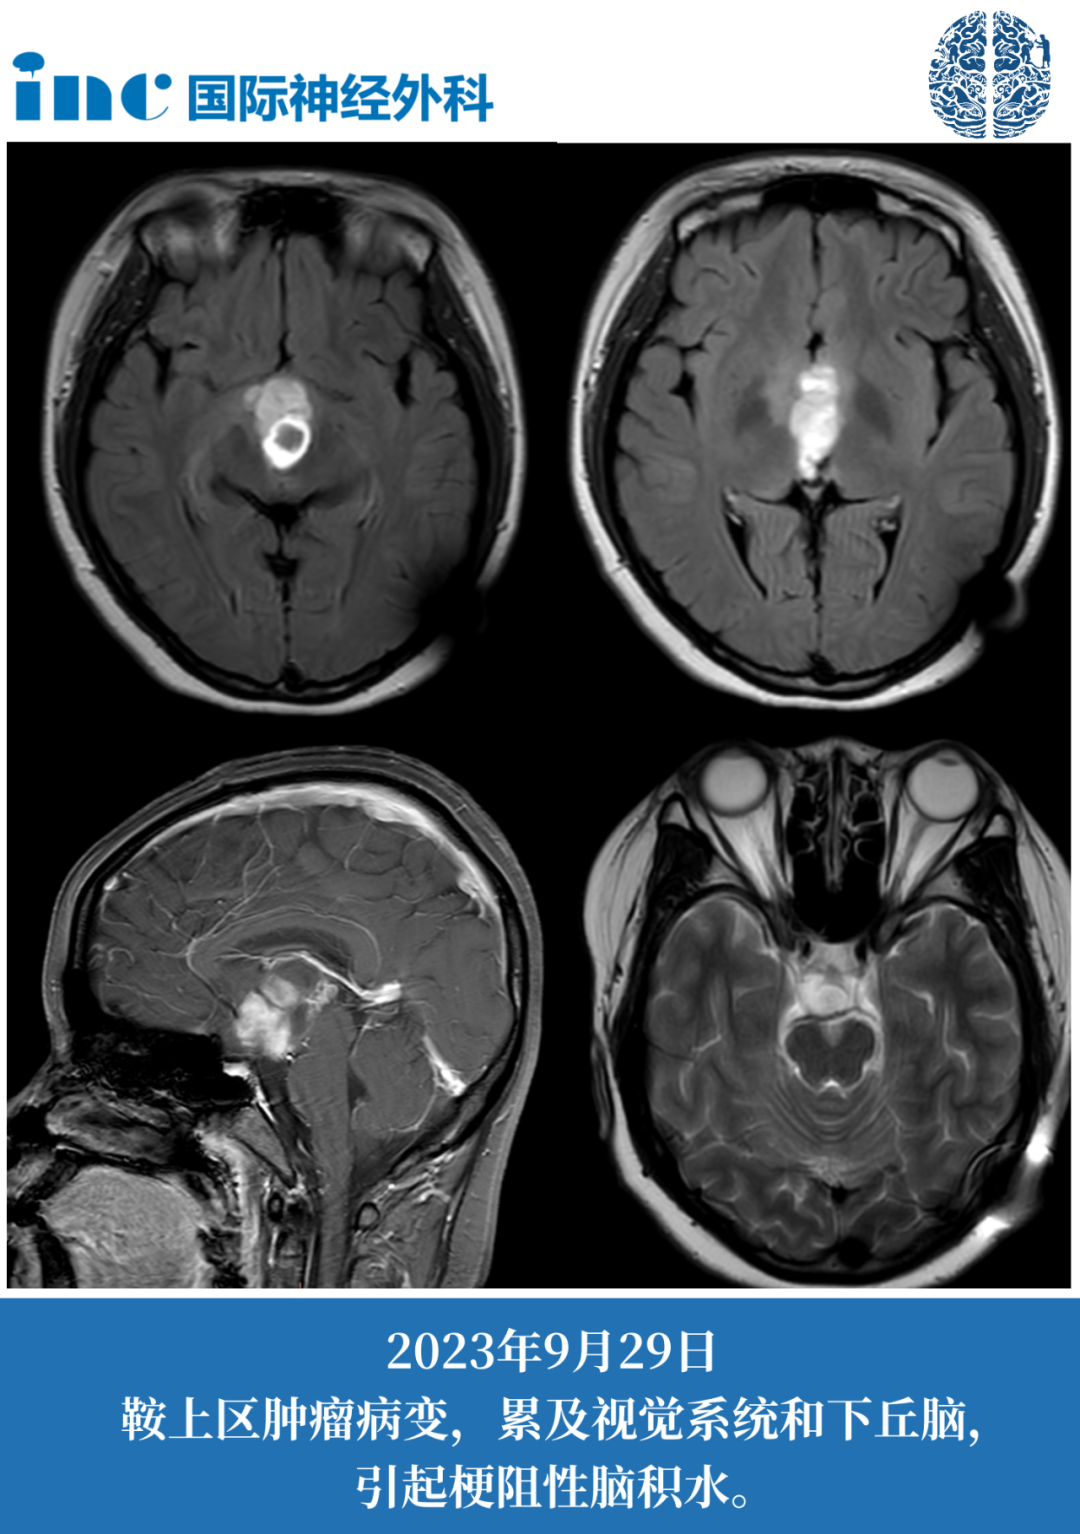

妙妙14岁女孩-鞍区占位性病变

术前症状:2016年,年仅7岁的女孩妙妙怀疑早熟,父母带着他去医院进一步检查发现,“罪魁祸首”竟是脑子里的肿瘤。虽然肿瘤是可以通过外科手术切除的,但妙妙的肿瘤位于鞍区,手术存在风险。医生建议定期复查,保守观察。2023年12月,妙妙症状再次加重,复查发现肿瘤有很明显的占位效应,危及视神经及视交叉(两者已经被肿瘤累及),有明确的手术指征。手术治疗不能再等,肿瘤一旦进一步增大,妙妙可能面临更严重的问题。

术后4天普通病房查房:妙妙可以下地行走,状态逐渐好转,巴教授告知术后核磁很好,肿瘤已经全切。